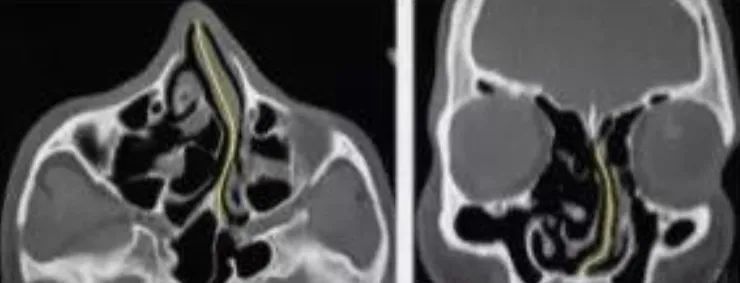

1.腺样体,扁桃体肥大, 惹起气道狭窄 ,使得从鼻腔进入的气流缺乏以支撑我们的呼吸,从而由于条件反射养成用嘴巴呼吸的习气。

2.过敏性鼻炎招致鼻分泌物增加,鼻痒,鼻塞,气道被阻塞。同时过敏性鼻炎和腺样体肥大还会互相影响,一朝一夕构成 腺样面子容 。

3.鼻中隔偏曲,鼻息肉,鼻甲肥大等其他鼻部异常。

所以不肯定本人是被动口呼吸还是主动口呼吸的姐妹,能够去医院拍个片子看一下, 有的放矢处理问题哦 !